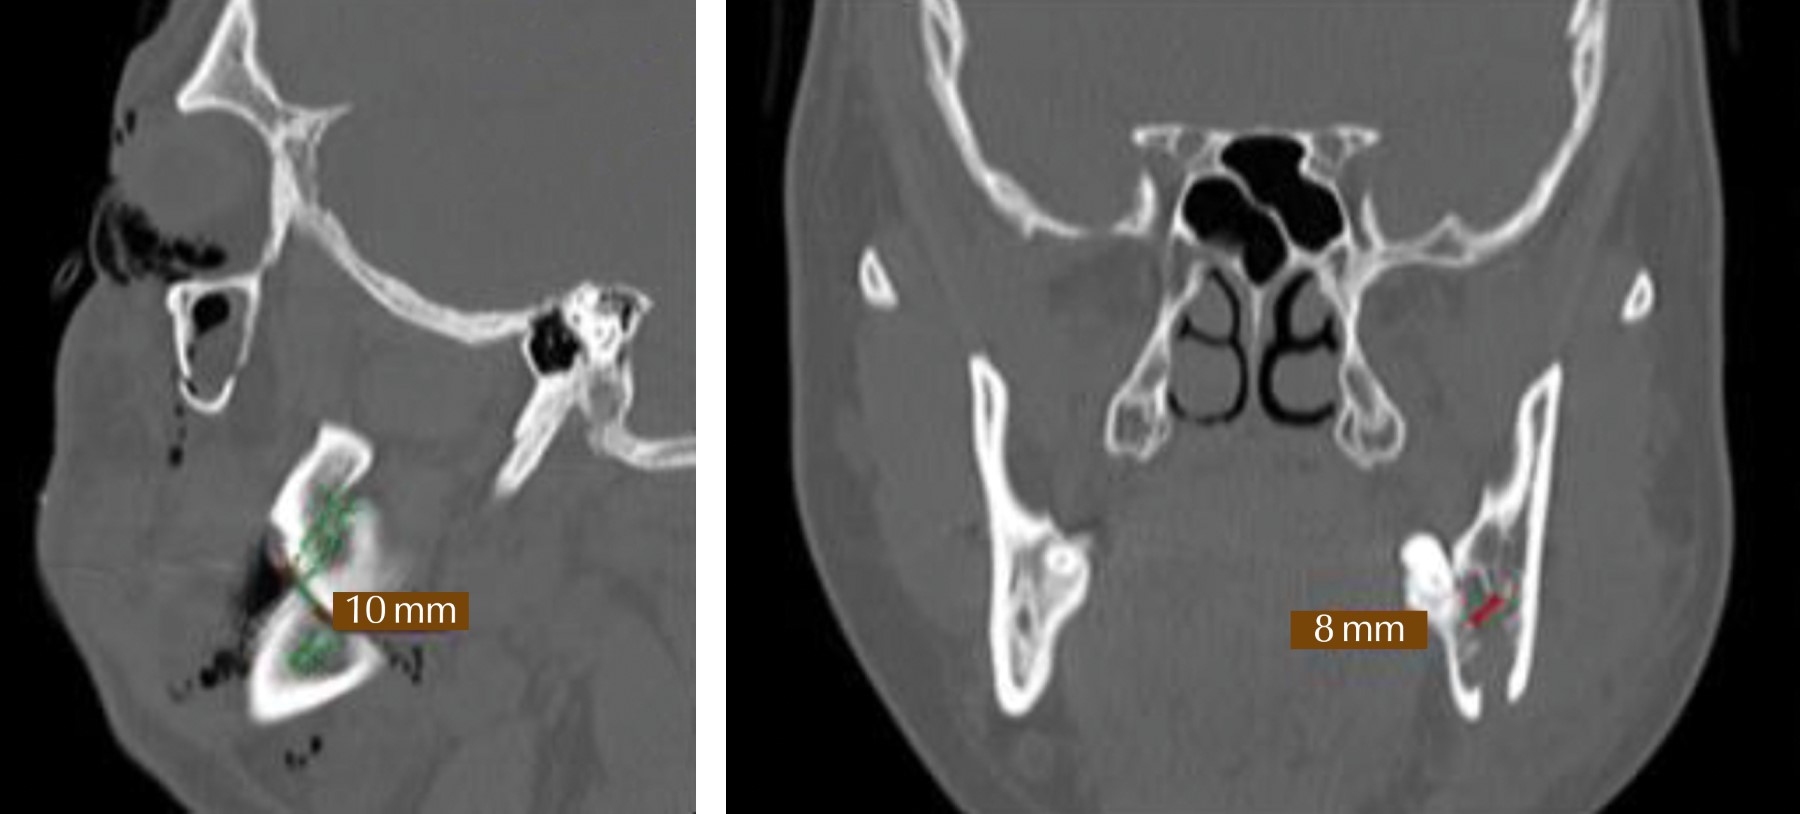

Para medir el grado de desplazamiento, se tomó como punto anatómico de referencia el techo del conducto del paquete neurovascular dentario inferior con el uso de la tomografía asistida por computador en sus cortes coronales y sagitales (Figura 4).

El objetivo principal de cualquier estudio es recopilar datos que tendrían un impacto positivo en el diagnóstico, el tratamiento y la prevención de una enfermedad. En la revisión de la literatura que se realizó no se menciona el uso de la tomografía asistida por computador como un instrumento de evaluación del grado de desplazamiento de la fractura. Para evaluar el grado de desplazamiento de los segmentos óseos mandibulares y la posición del tercer molar en los cortes sagitales y coronales, se tomó en consideración el techo del conducto dentario inferior.

En este estudio se da a conocer la aportación de una nueva clasificación para evaluar el desplazamiento de los fragmentos óseos de la fractura de ángulo mandibular, en el que se utilizó la tomografía asistida por computador (TAC) para medir la distancia del techo del conducto dentario inferior, presente en cada fragmento de la fractura, lo cual es una constante anatómica en cada individuo.